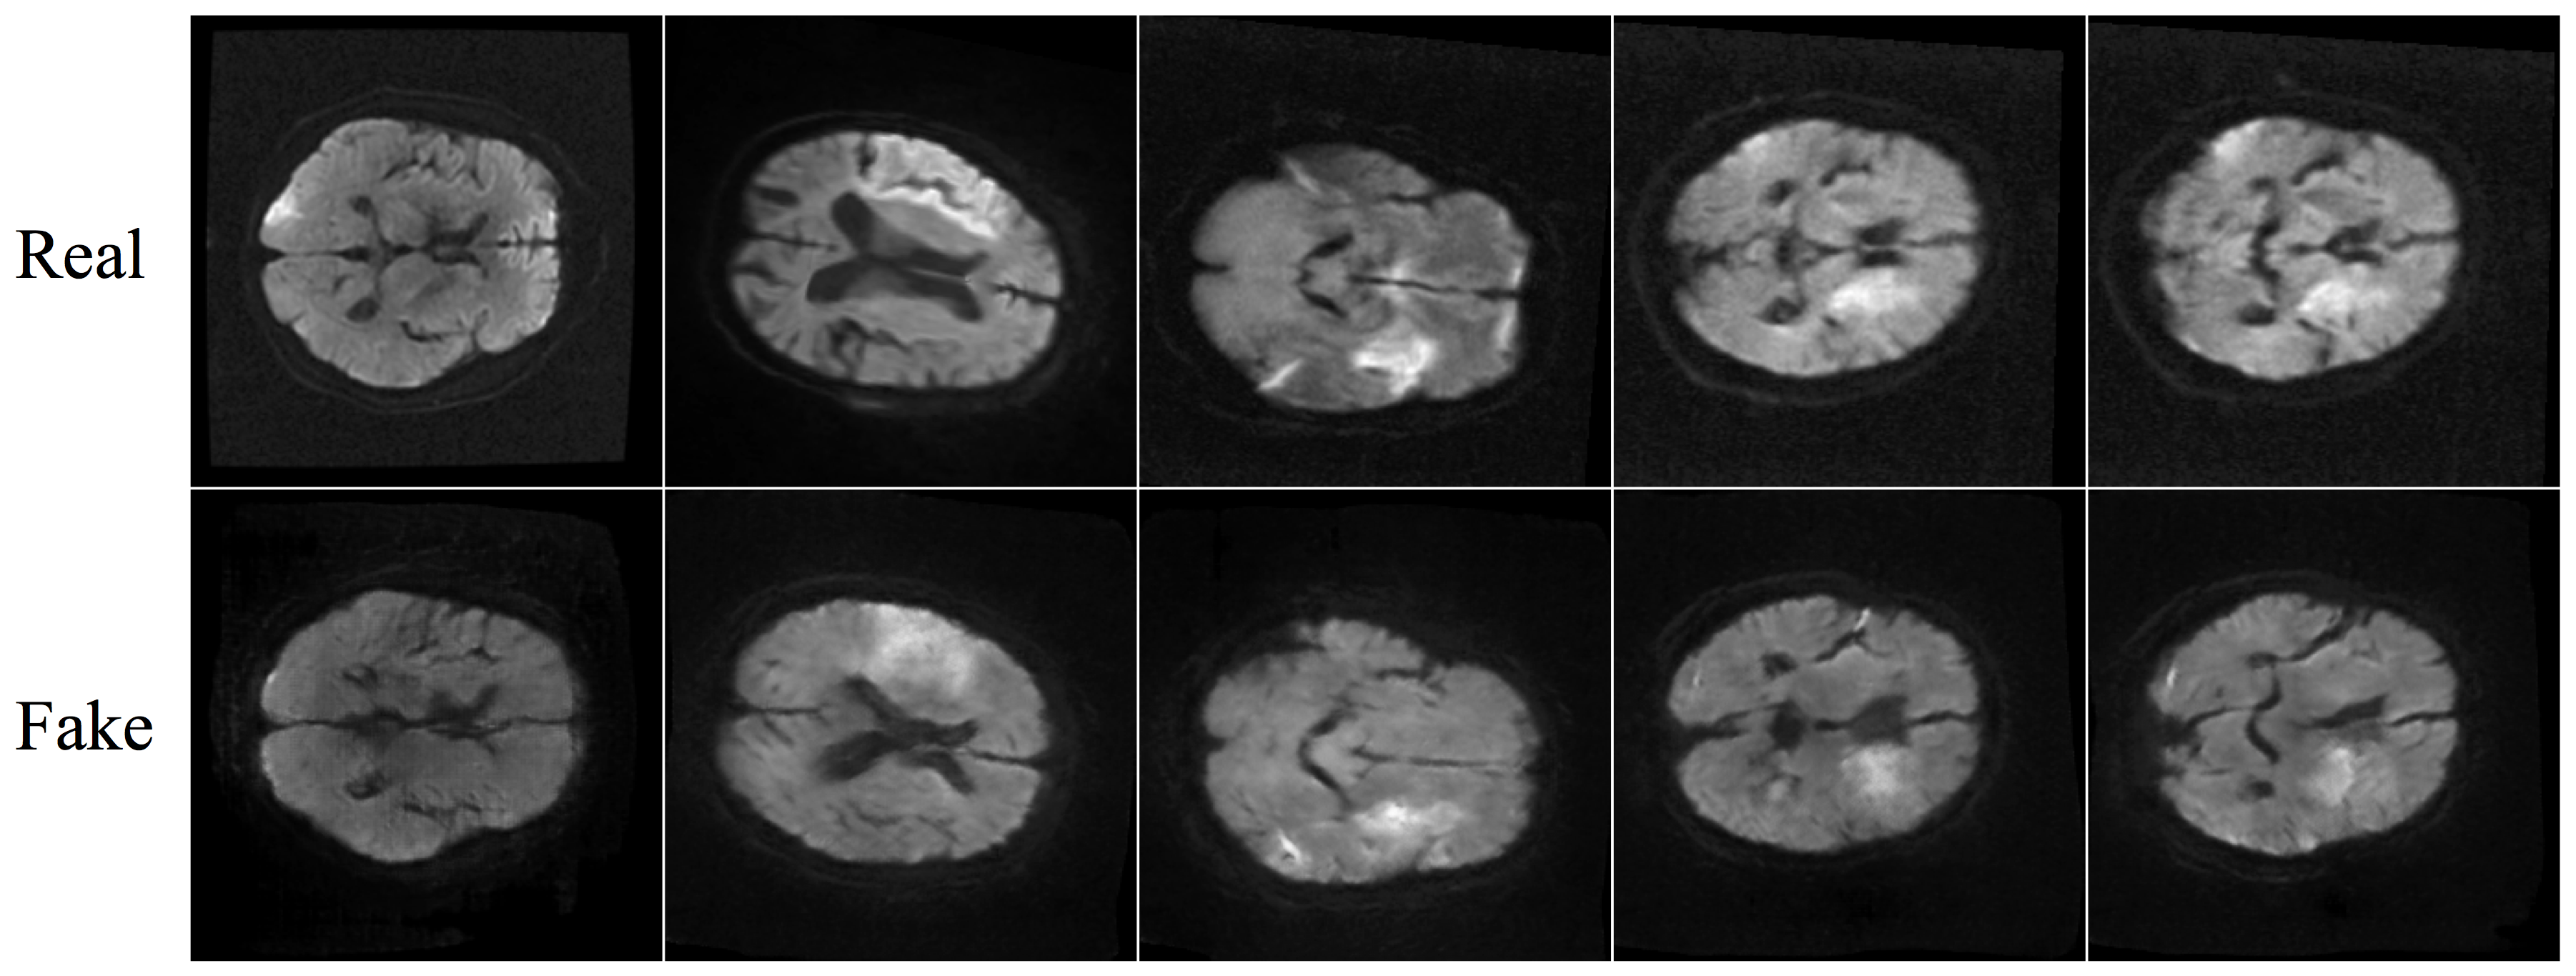

Refer to caption

Figure 2: Examples of real and derived MR slices. The top row shows real images and the bottom row shows slices generated from the CT-To-MR Conditional GAN model.

We present qualitative results produced by the CT-To-MR CGAN and quantitative results of training FCN models with and without derived MR inputs. Fig. 2 shows a subset of results created by the CT-To-MR CGAN model. Five MR slices are shown that were generated by conditioning on CTP input from a 20% test-set. The top row shows the ground truth MR slice and the bottom row shows the corresponding slice that was created by the CT-To-MR generator. While only a qualitative assessment, it can be seen that hyperintense regions within the ground truth DWI image are approximately replicated by the conditional generator.